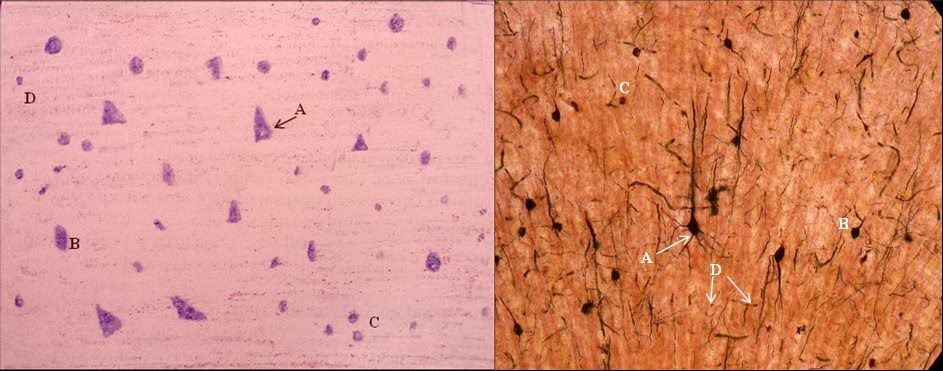

2. Neuronas

1. Partes

1. Soma

1. Núcleo

1. Sustancia de Nissl

2. Axón

1. Nódulos de Ranvier

1. Cono axónico

2. Botones terminales

1. Telodendrón

2. Tipos

1. Por función

1. Sensoriales

1. Motoras

1. Interneuronas

2. Por prolongaciones

1. Presudomonopolar

1. Monopolar

1. Multipolar

1. Bipolar